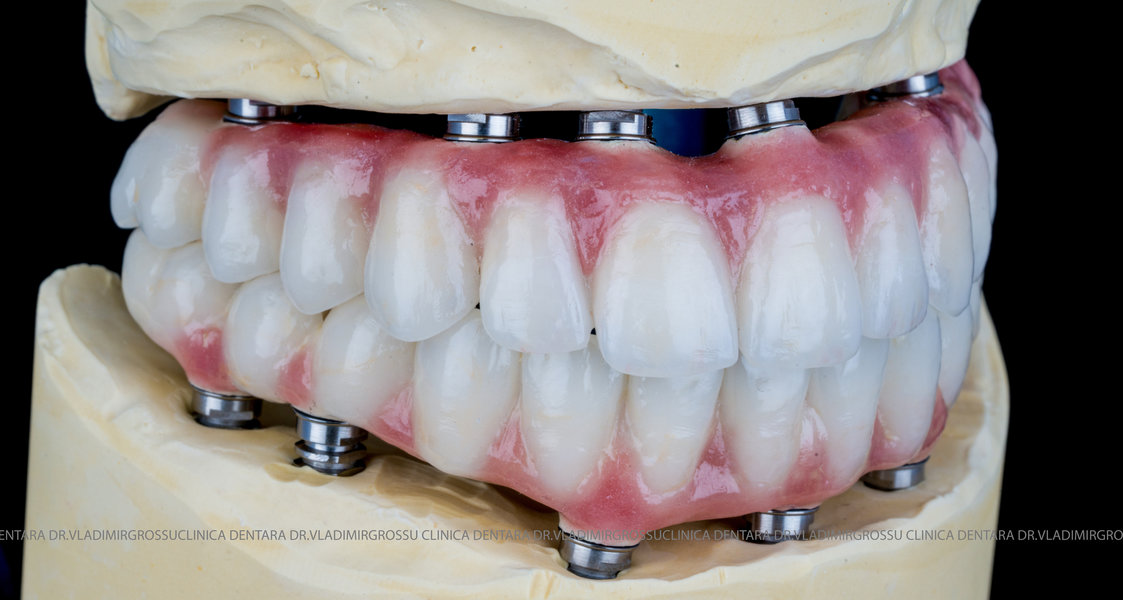

Cazuri clinice conceptul All-on-6